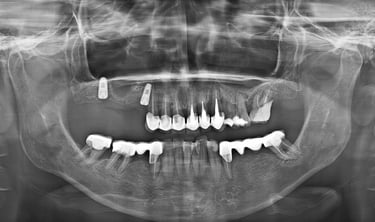

Inserare 2 implanturi in cadranul III si un implant inserat post-extractional in cadranul IV